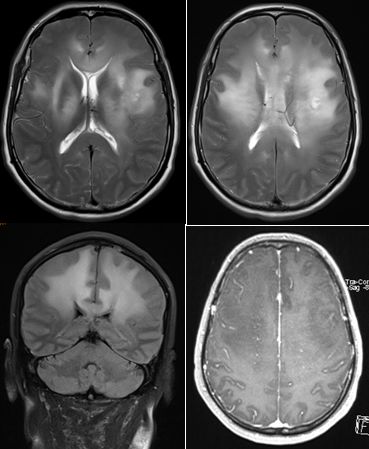

26岁,男,突发右眼视力障碍和精神状态改变入院。

11月后复查头部CT,如下图:

答案:线粒体脑肌病伴乳酸酸中毒及中风样发作(MELAS)

患者青年男性,卒中样起病,MRA未见明显异常,有好多老师想到静脉系统梗死,患者影像病灶并不符合静脉引流分布,答案是线粒体脑肌病伴乳酸酸中毒及中风样发作(MELAS)。其特征为轻度活动后即感疲乏无力,休息后好转;肌肉活检可见破碎红纤维。常以卒中样发作、痴呆、癫痫和共济失调等为主要表现。病灶影像特点与脑梗死类似,也可呈多发性、对称性、迁移性脑梗死样病变。皮层层状异常信号是其特征性影像表现。鉴别诊断有栓塞或夹层所致的真正的缺血性卒中、亚急性坏死性脑脊髓病(Leigh 脑病)、血管炎和癫痫等。